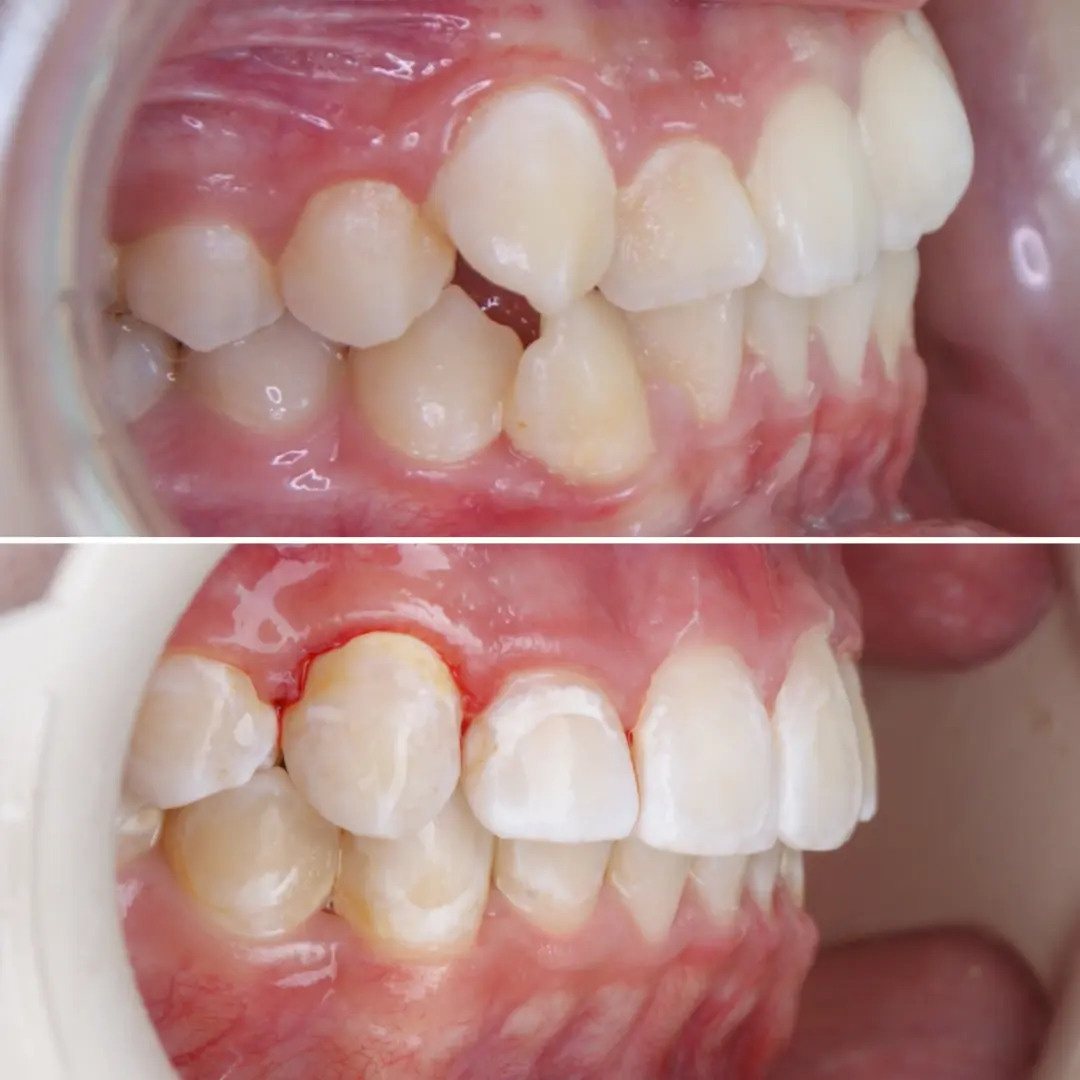

✔Вот такая ортодонтическая микроподготовка к художественной реставрации зубов... Мелочи очень важны👆